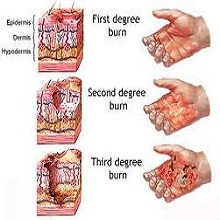

Повреде високом температуром се најчешће догађају случајно, на радном месту, у саобраћајним и рударским несрећама, пожарима, али нису ретке ни у домаћинству. Опекотине настају деловањем врелих течности, пара пламена, топлотног зрачења, електричне струје, хемикалија и радиоактивног зрачења. Оштећења могу да захвате различите слојеве ткива. |